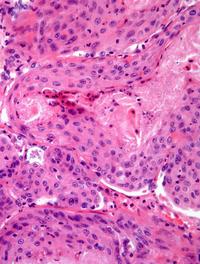

Le cancer bronchique non à petites cellules (CBNPC) dans sa variété épidermoïde représente 20 à 30 % de tous les cancers bronchiques. [...]

Parmi les anomalies moléculaires décelables dans les cancers du poumon non à petites cellules (CNPC), le réarrangement du gène ALK [...]

L’une des caractéristiques du cancer et notamment du cancer bronchique est sa capacité à contourner la réponse immunitaire. PD-1 (programmed [...]

Le cancer du poumon à petites cellules (KBP-PC) représente 13 % de l’ensemble des tumeurs malignes pulmonaires. Il est souvent découvert [...]